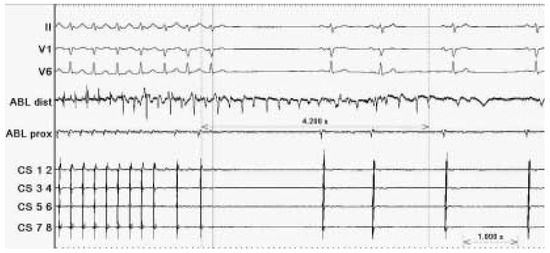

Case description A 70-year-old former athlete complained about a twenty-year history of paroxysmal atrial fibrillation with onset at rest and during the night, which became persistent in the last three years [...]